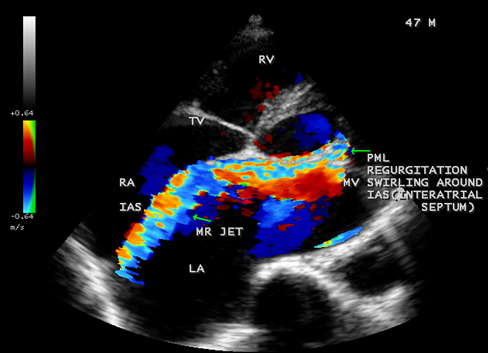

Case 2. PML (posterior mitral leaflet) prolapse causing severe mitral regurgitation with aneurysmal LA (left atrium) as shown in Figures 3 to 8 due to PML chordal rupture of rheumatic etiology in a 47- year old male. Patient was advised lifelong penicillin prophylaxis and MVR (mitral valve replacement).

Figure 8. Tilted apical view showing the PML regurgitation swirling around the IAS (interatrial septum) in a 47-year-old male and the left atrium is aneurysmally dilated